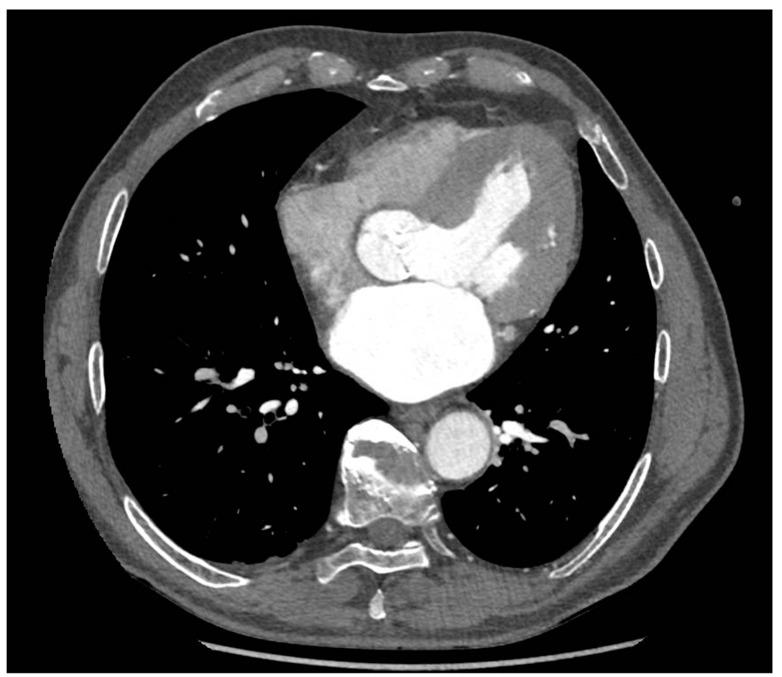

Transcatheter aortic valve implantation (TAVI) is currently becoming the method of choice in high-risk patients with severe aortic valve stenosis. Post-TAVI complications are more common owing to the increasing use of the method. The majority of TAVI complications derive from concomitant aortic stenosis with moderate/severe aortic insufficiency, paravalvular leak, and atrioventricular block. The contemporary TAVI qualification process includes a thorough echocardiography and angio-CT of the aorta, which is crucial in assessing valve measurements, determining the position of the coronary arteries branching from the aorta, and choosing the optimal valve size. We present the case report of an 81-year-old patient admitted to our hospital because of exacerbation of the clinical condition and development of pulmonary edema a few days after TAVI. Despite the reduction of the initial leak, an echocardiographic examination revealed the remaining severe paravalvular aortic leakage. We performed open-heart cardio-thoracic surgery, explanted the TAVI valve, and implanted the biological prosthesis (Edwards Perimount Magna size 25). Introduction of new interventional treatment approaches and the availability of imaging tools have substantially reduced the incidence of significant paravalvular leak and offered a better prognosis for patients undergoing TAVI.

经导管主动脉瓣植入术(TAVI)目前正成为重度主动脉瓣狭窄高危患者的首选治疗方法。由于该方法使用的增加,TAVI术后并发症更为常见。大多数TAVI并发症源于合并中度/重度主动脉瓣关闭不全的主动脉狭窄、瓣周漏和房室传导阻滞。当代TAVI的评估过程包括全面的超声心动图检查和主动脉血管造影CT,这对于评估瓣膜尺寸、确定从主动脉分支的冠状动脉位置以及选择最佳瓣膜大小至关重要。我们报告了一例81岁患者,因TAVI术后几天临床症状加重和肺水肿发展而入院。尽管初始漏血减少,但超声心动图检查显示仍存在严重的瓣周主动脉瓣反流。我们进行了心脏直视胸外科手术,取出TAVI瓣膜,并植入生物假体(爱德华兹Perimount Magna尺寸25)。新介入治疗方法的引入和成像工具的应用显著降低了严重瓣周漏的发生率,并为接受TAVI的患者提供了更好的预后。